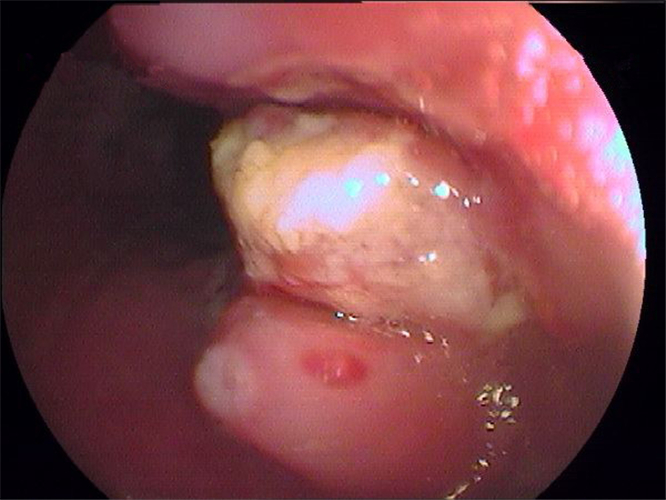

淺表型糜爛出血慢性胃炎

淺表型糜爛慢性胃炎